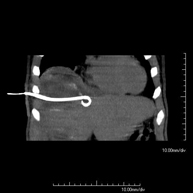

- Drenaje abdominal guiado por TC (abscesos, colecciones) Consiste en colocar un catéter de drenaje sobre una colección líquida localizada en la cavidad abdominal, con la intención de vaciar el máximo posible dicha colección. El paciente deberá mantener el drenaje algunos días, normalmente hasta que no sea productivo. A menudo se realiza bajo sedación, con la ayuda del equipo de anestesia. Todo el procedimiento se realiza controlado con imágenes obtenidas por Tomografía Computarizada (TC) en varios momentos de la prueba mediante el empleo de Fluoroscopia-TC. Tras la prueba, el paciente permanece hospitalizado. Es necesario aportar pruebas de coagulación antes de la prueba. Consiste en colocar un catéter de drenaje sobre una colección líquida localizada en la cavidad abdominal, con la intención de vaciar el máximo posible dicha colección. El paciente deberá mantener el drenaje algunos días, normalmente hasta que no sea productivo. A menudo se realiza bajo sedación, con la ayuda del equipo de anestesia. Todo el procedimiento se realiza controlado con imágenes obtenidas por Tomografía Computarizada (TC) en varios momentos de la prueba mediante el empleo de Fluoroscopia-TC. Tras la prueba, el paciente permanece hospitalizado. Es necesario aportar pruebas de coagulación antes de la prueba.

- Drenatge abdominal guiat per TC Consisteix en col·locar un catèter de drenatge sobre una col·lecció líquida localitzada en la cavitat abdominal, amb la intenció de buidar el màxim possible d'aquesta col·lecció. El pacient haurà de mantenir el drenatge uns quants dies, normalment fins que no sigui productiu. Sovint es realitza sota sedació, amb l'ajuda de l'equip d'anestèsia. Tot el procediment es realitza controlat per imatges obtingudes per Tomografia Computaritzada (TC) en diversos moments de la prova mitjançant l'ús de Fluoroscòpia-TC. Després de la prova, el pacient resta hospitalitzat. És necessari que porti proves de coagulació abans de la punció. Consisteix en col·locar un catèter de drenatge sobre una col·lecció líquida localitzada en la cavitat abdominal, amb la intenció de buidar el màxim possible d'aquesta col·lecció. El pacient haurà de mantenir el drenatge uns quants dies, normalment fins que no sigui productiu. Sovint es realitza sota sedació, amb l'ajuda de l'equip d'anestèsia. Tot el procediment es realitza controlat per imatges obtingudes per Tomografia Computaritzada (TC) en diversos moments de la prova mitjançant l'ús de Fluoroscòpia-TC. Després de la prova, el pacient resta hospitalitzat. És necessari que porti proves de coagulació abans de la punció.